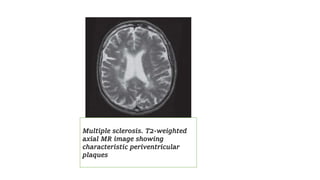

Multiple sclerosis. T2-weighted

axial MR image showing

characteristic periventricular

plaques